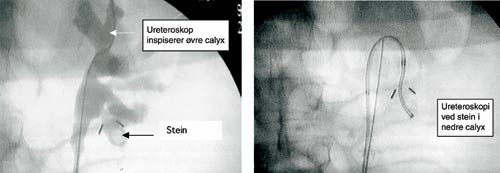

Endoskopisk kirurgi i ureter og i nyren via ureter er blitt mulig grunnet en revolusjonerende utvikling av endoskopiske instrumenter og knusemetoder de siste 20 år. Instrumentene er stadig blitt tynnere, den fiberoptiske kvaliteten er forbedret, og nye ledere, kurver og stenter er blitt tilgjengelige. Fleksible ureteroskoper tillater i dag retrograd kirurgi i nyrebekken og calyces (fig 3). Denne utviklingen har gjort metoden sikrere, og har medført kontinuerlig utvidelse av indikasjonsområdet for intraureteral diagnostikk og behandling (6) – (9).

Indikasjon. Metoden benyttes i steinbehandling i hele ureter. I Norge er metoden den mest anvendte når det gjelder stein i distale og midtre ureter (1). Fleksible instrumenter benyttes også i nyrebekkenet i situasjoner hvor sjokkbølgebehandling og perkutan nefrolitotomi er mindre egnet. Kompliserte tilfeller krever kombinasjon av flere metoder.

Det tynne kikkertinstrumentet (ureteroskopet) føres inn i ureter over en leder via urinrøret og urinblæren under synets ledelse. Mange benytter røntgengjennomlysning som et supplement. Ureteroskopet føres opp til ønsket posisjon. Steinene hentes ut ved hjelp av spesielle kurver, eller knuses med endoskopiske knusesonder (ultralyd, holmiumlaser, elektrohydraulisk, mekanisk). De mer kompliserte behandlingene avsluttes med at man legger inn en ureterstent som pasienten har liggende inne i 1 – 2 uker.